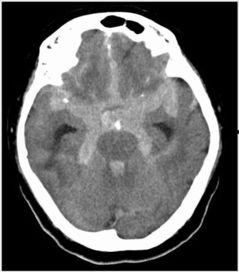

三、动脉破裂的图片:一场视觉盛宴

这张动脉破裂的图片,让我感受到了医学影像的强大力量。图片中,我们可以清晰地看到破裂的动脉血管,血液喷涌而出,场面触目惊心。下面,就让我们一起来欣赏这张神奇的图片。